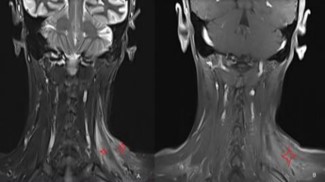

A 49-year-old female patient applied to the medical oncology unit in August 2019 due to a mass in her left breast. After the necessary tests, invasive breast cancer was detected in the biopsy, and breast-conserving surgery was performed. Afterwards, 3 cycles of docetaxel + cyclophosphamide chemotherapy and a total of 60 Gy radiotherapy in 30 fractions were given. Recurrence occurred in the same area in September 2020. After 4 cycles of doxorubicin + cyclophosphamide and 12 cycles of paclitaxel, modified radical mastectomy was performed, and oral capecitabine was started. Approximately one year later, recurrence was detected in the cervical and supraclavicular regions, and 45 Gy radiotherapy in 20 fractions and 6 cycles of gemcitabine were applied. Four weeks after the last chemotherapy, redness, pain, and swelling developed in the left supraclavicular region. In the evaluation made by medical oncology, weakness was detected in the left shoulder and upper extremity. She was referred to our pain clinic for the preliminary diagnosis of radiation-induced brachial plexopathy and pain palliation. On examination, neck deviation to the left, increased left shoulder height, and Sternocleidomastoid (SCM) muscle contracture were detected. Right neck rotation limitation, severe pain on palpation of the neck region, and color change were observed. In addition, there was moderate loss of strength in shoulder abduction and arm extension on muscle strength examination (Figure 1). McGill pain score was 92, and Visual Analog Scale (VAS) score was 9 points. In our Ultrasonography (USG) evaluation, we observed hyperechogenicity in the SCM, trapezius, and scalene muscles (Figure 2). In magnetic resonance imaging, we observed hyperintensity in the T2 phase and contrast enhancement in T1 in the same muscle groups (Figure 3). Gemcitabine treatment was stopped with the diagnosis of gemcitabine-associated radiation recall myositis. We started the treatment with drugs such as prednisolone, ibuprofen, and paracetamol + tramadol. However, despite 5 weeks of treatment, the symptoms did not regress. A 70% loss in sleep quality and daily life activities was observed due to pain. We applied dexamethasone and lidocaine to the SCM, trapezius, and scalene muscles under USG guidance. VAS decreased from 9 to 7 within a week. Afterwards, 100 IU abobotulinum toxin A was applied to the same muscles [8]. After one month, the VAS score decreased to 2. The need for analgesics decreased to 2 tablets of ibuprofen in the last month. The contracture almost completely resolved (Figure 4). The McGill score was measured as 20. Written informed consent was obtained from the patient for publication of this case report and accompanying images.

Figure 3: On magnetic resonance imaging, T2-weighted sequences show hyperintensity in the left sternocleidomastoid and scalene muscles (small stars) (A). On T1 contrast-enhanced sequences, mild contrast enhancement and hyperintensity are observed in the sternocleidomastoid and scalene muscles (large stars) (B).